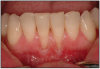

Gingival recession is defined as the reduction of the height of the marginal gingiva to a location apical to the cementoenamel junction, resulting in root surface exposure (Figure 11). Gingival recession can be precipitated by many factors including increasing age, gender, and anatomical factors. Toothbrushing technique, frequency, duration, force of brushing, and the hardness of toothbrush filaments may also contribute to gingival recession.36

Figure 11 – Gingival Recession

Figure 11